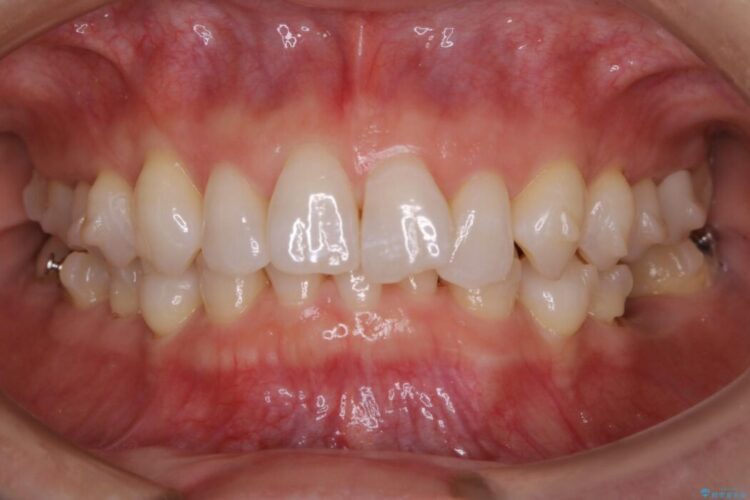

噛み合わせも改善され、一番最初の目的であった歯列もきれいに整いご満足いただけました。